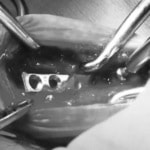

トイプードル 右遠位橈尺骨短斜骨折のALPSによる内固定

当院ではAdvanced Locking plate system(ALPS)と、Locking compression plate system(LCPS)という骨接合法で骨折症例の治療を行っています。

Advanced Locking Plate System

従来型のプレートのように広い面積で骨と接するプレートを用いて固定を行った場合、プレート下の骨はプレートとの接触面において血行が絶たれ壊死し、それがリモデリングされると骨密度が低下する。この骨密度の低下防ぐために、骨折部局所への血行を温存することの重要性が近年改めて認識されるようになってきている。Advaed Locking Plate System (ALPS)は従来型のプレートシステムの欠点を改良し、より使いやすく、より骨への血行を阻害しないようにというコンセプトで作られた。